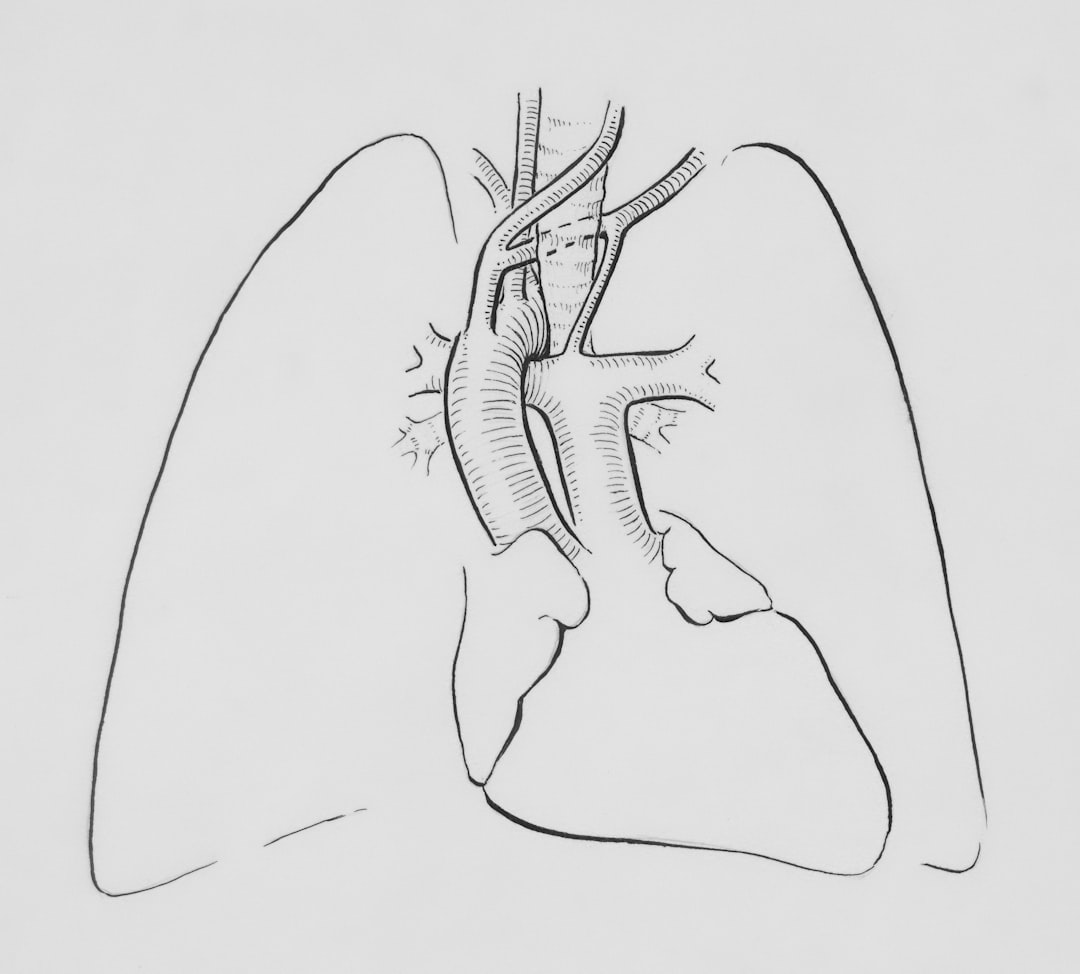

기흉은 폐와 흉벽 사이의 공간에 공기가 축적되는 상태를 말합니다. 이로 인해 폐의 확장과 수축이 방해받아 호흡이 어려워지며, 경우에 따라 심각한 합병증으로 이어질 수 있는 상황입니다. 기흉은 대개 외부 충격이나 심한 기침, 혹은 선천적인 폐의 이상으로 발생할 수 있습니다. 폐를 둘러싸고 있는 흉막이 손상되면서 공기가 들어가게 되는 것이죠. 이를 알고 있으면 기흉에 대해 더욱 경각심을 가질 수 있습니다.